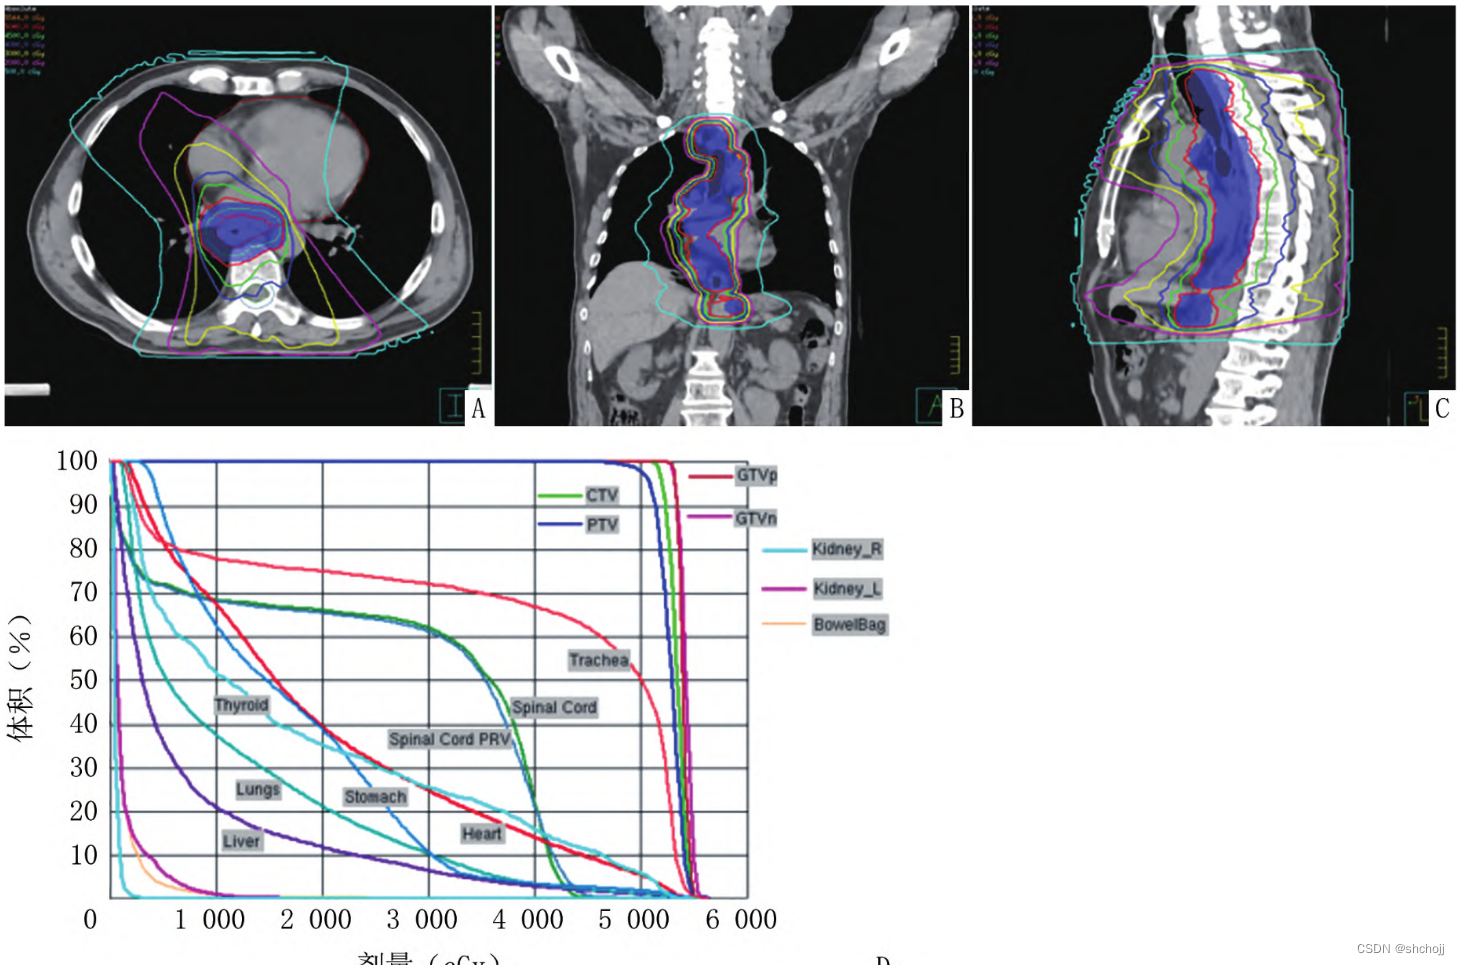

剂量体积直方图(dose volume histogram,DVH):

- 一维剂量度量为可接受一定剂量照射的器官体积,或一定体积的照射剂量

- 二维剂量刻度为DVH曲线上点代表剂量或者体积的绝对值(Gy/cc)和相对值(%)

- DVH不能提供剂量的三维空间分布,而定位CT上三维图像可以显示某等剂量曲线相对于OAR的空间分布。

同步加量技术(simultaneous integrated boost,SIB):在头颈及胸腹部恶性肿瘤放疗中得到广泛应用,主要优势在统一计划内针对不同区域给予差异性剂量分配。SIB计划评估与常规IMRT计划评估类似,关键在与确认不同梯度处方剂量均能满足治疗需求。

三维剂量分布:不同轴面逐层分析;

审计各靶区是否按照预设剂量分布覆盖,并达到预期目标

正常组织所受剂量的范围及空间分布

PTV:处方剂量覆盖。

CTV、GTV:易复发

OAR:PTV外处方剂量保护

- DVH评估OAR受量